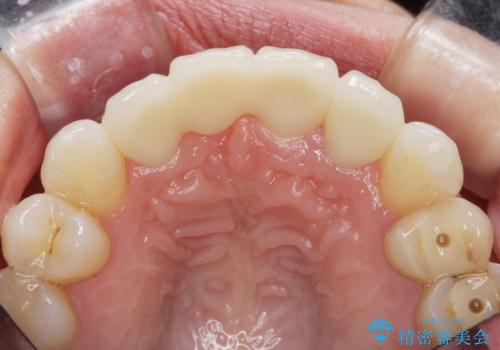

- 44万円(仮歯・ジルコニアクラウン×4)費用は治療当時の料金となります

欠損部の歯ぐきの量が足りない場合は、移植を行い歯肉を増大させることもありますが、今回は仮歯で様子を見た結清掃性・審美性に問題が出なかったので行いませんでした。